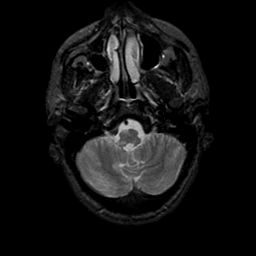

MR Study #9, April 14, 1991 -- Slice #8

[Home][Help][Clinical][Tour 1][Tour 2] Slice 8